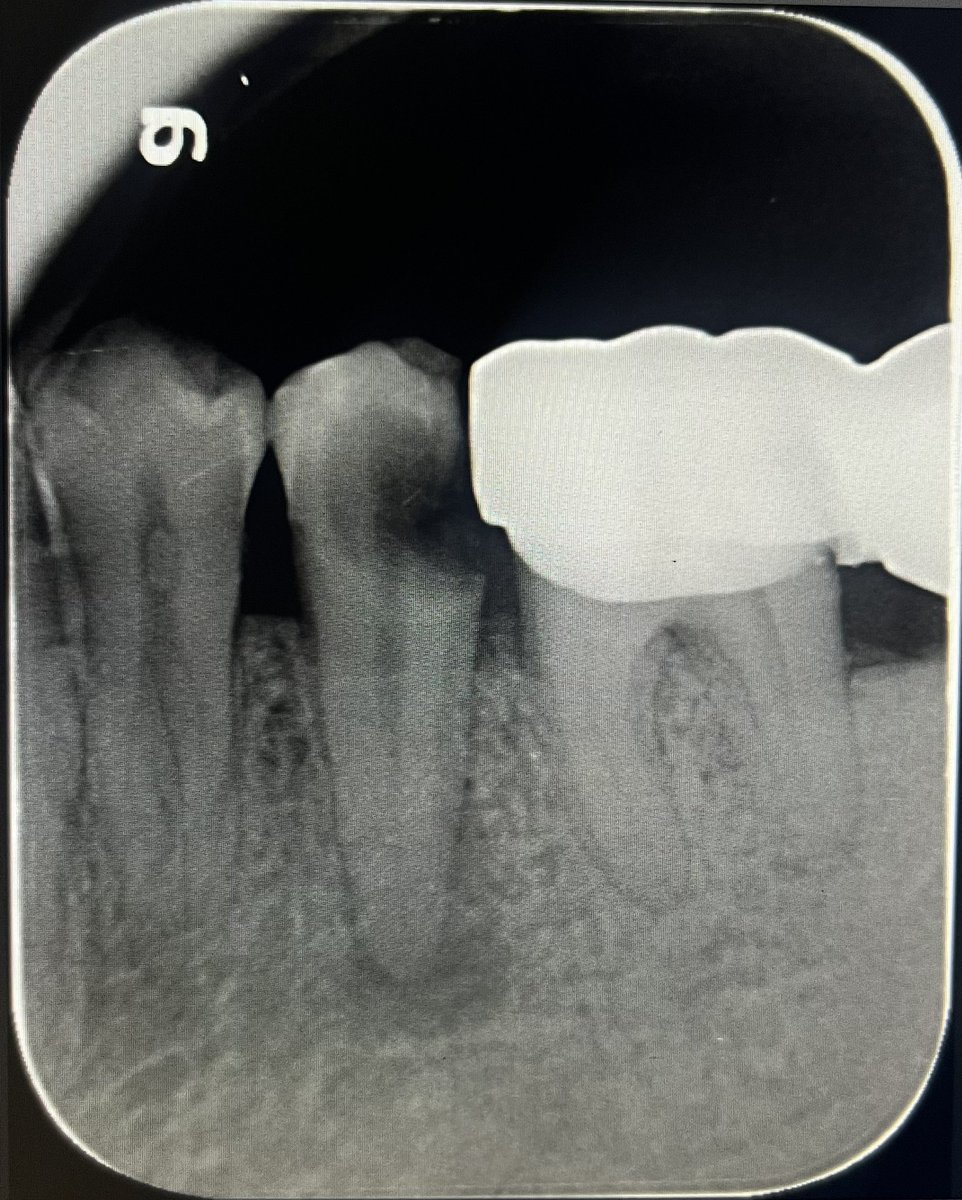

حالة جميلة لصباح اليوم 🙏🏻

Root Canal Treatment #34

Dx:SIP+SAP

Gingival overgrowth and deep caries in the distal wall, Rebuild the distal wall to achieve optimum isolation ✨

Next Step: Crown